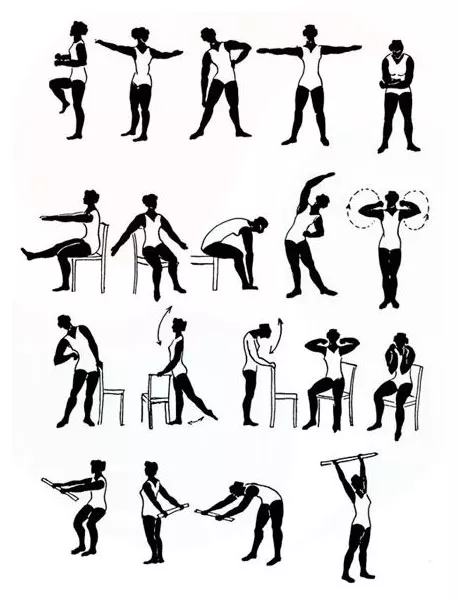

- Физиопроцедуры и лечебная гимнастика.

Лечение бронхиальной астмы должно сочетать в себе средства, способствующие быстрому расширению бронхов и устранению приступа, противовоспалительные препараты, ингаляции, исключение контакта с выявленным аллергеном, а также ежедневную влажную уборку.

- активный образ жизни и физические нагрузки;

Отличный эффект позволяют достичь отвары из адониса, мелиссы, ромашки, тысячелистника, мяты, зверобоя, чабреца, фенхеля с медом. Для улучшения ритма не лишним будет пройти курс иглоукалывания, точечного массажа, занятий лечебной йоги и релаксирующие дыхательные методики.